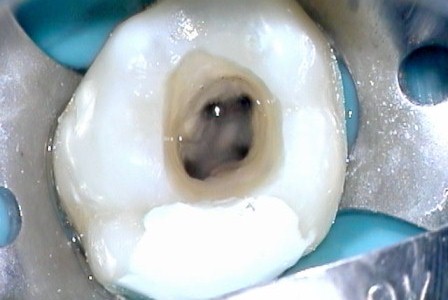

Попробуем ответить на вопрос, как лечить пульпит? Существует несколько методов лечения пульпита. Выбор зависит от множества факторов, в первую очередь, типа и выраженности воспалительного процесса, а также состояния зуба. Чаще всего используют следующие:

- Консервативная терапия. Чтобы снять воспаление врач делает накладки, пропитанные антибиотиками, для устранения воспаления, а также использует специальные выщелачивающие полость зуба аппликации. Они стимулируют выработку компенсаторного дентина, благодаря чему зуб восстанавливается.

- Если это невозможно, воспаление слишком сильное, имеются признаки гнойного процесса или другие противопоказания к консервативному лечению, то врач может выбрать удаление пульпы. Делается это в одно или два посещения. В первом случае под анестезией врач удаляет пульпу и пломбирует канал. Во втором случае в камеру закладывается специальное вещество, которое вызывает отмирание пульпы. В народе его называют мышьяком, но этот элемент в нем давно не используется. После удаления пульпы воспаления уже не может быть, но зуб становится «мертвым»: невозможна выработка третичного дентина, он постепенно темнеет и начинает крошиться.